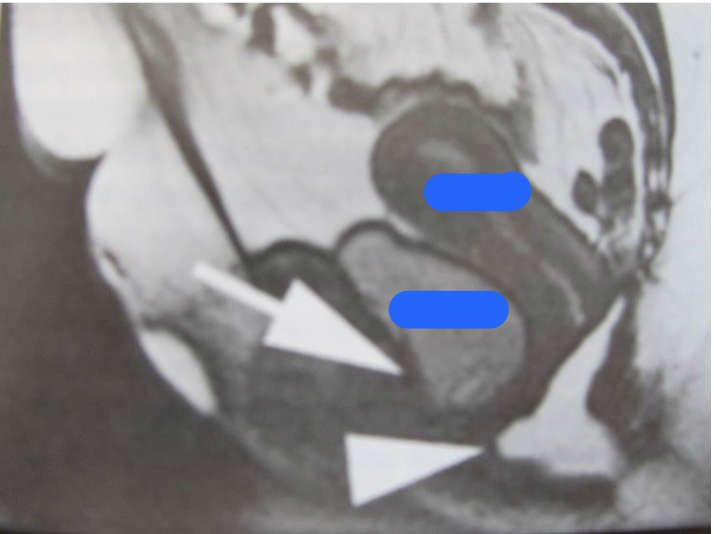

Identify the organs. And the dz process?

Top: Uterus

Bottom: Bladder

Dz process: Rectocele